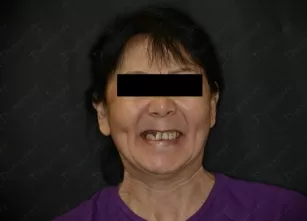

Фото работ